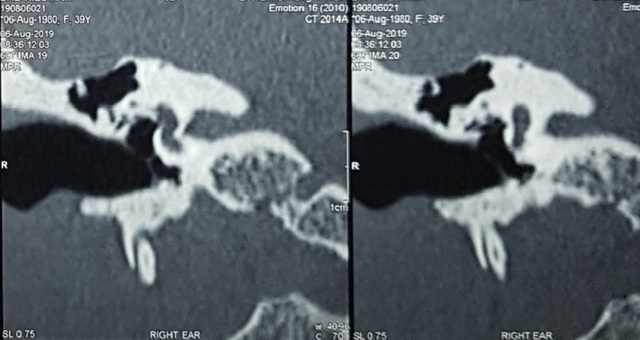

Tại đây, các bác sĩ tiếp tục chẩn đoán bệnh nhân bị viêm tai giữa mạn tính thủng nhĩ tai phải. Sau 1 tuần sử dụng kháng sinh tai bệnh nhân hết chảy dịch nhưng tình trạng đau đầu vấn dữ dội, kèm theo mờ mắt phải, hàm răng trên đau buốt. Các bác sĩ quyết định kiểm tra hình ảnh, truy tìm nguyên nhân của tình bệnh nhưng trên phim CT-Scan không phát hiện bất thường. Căn cứ trên bệnh sử về can thiệp vá màng nhĩ người bệnh đã được thực hiện, bác sĩ quyết định phẫu thuật mở thượng nhĩ để kiểm tra.

Kết quả phẫu thuật ghi nhận vùng màng não phía sau của bệnh nhân bị mất xương một (khoảng 1x2cm) nên tiến hành đặt mảnh vá trên cán búa. Trước khi đóng vết mổ, ê kíp phẫu thuật dùng kính hiển vi để kiểm tra thì phát hiện gần vị trí bị khuyết xương đang chảy dịch dịch não tủy. Ngay sau đó các phẫu thuật viên đã tiến hành tạo vạt cân cơ thái dương xử lý thành công vị trí bị rò dịch. 1 tuần sau phẫu thuật, bệnh nhân đã ăn uống bình thường, hết nhức đầu, chóng mặt, mờ mắt phải và ngủ ngon giấc.